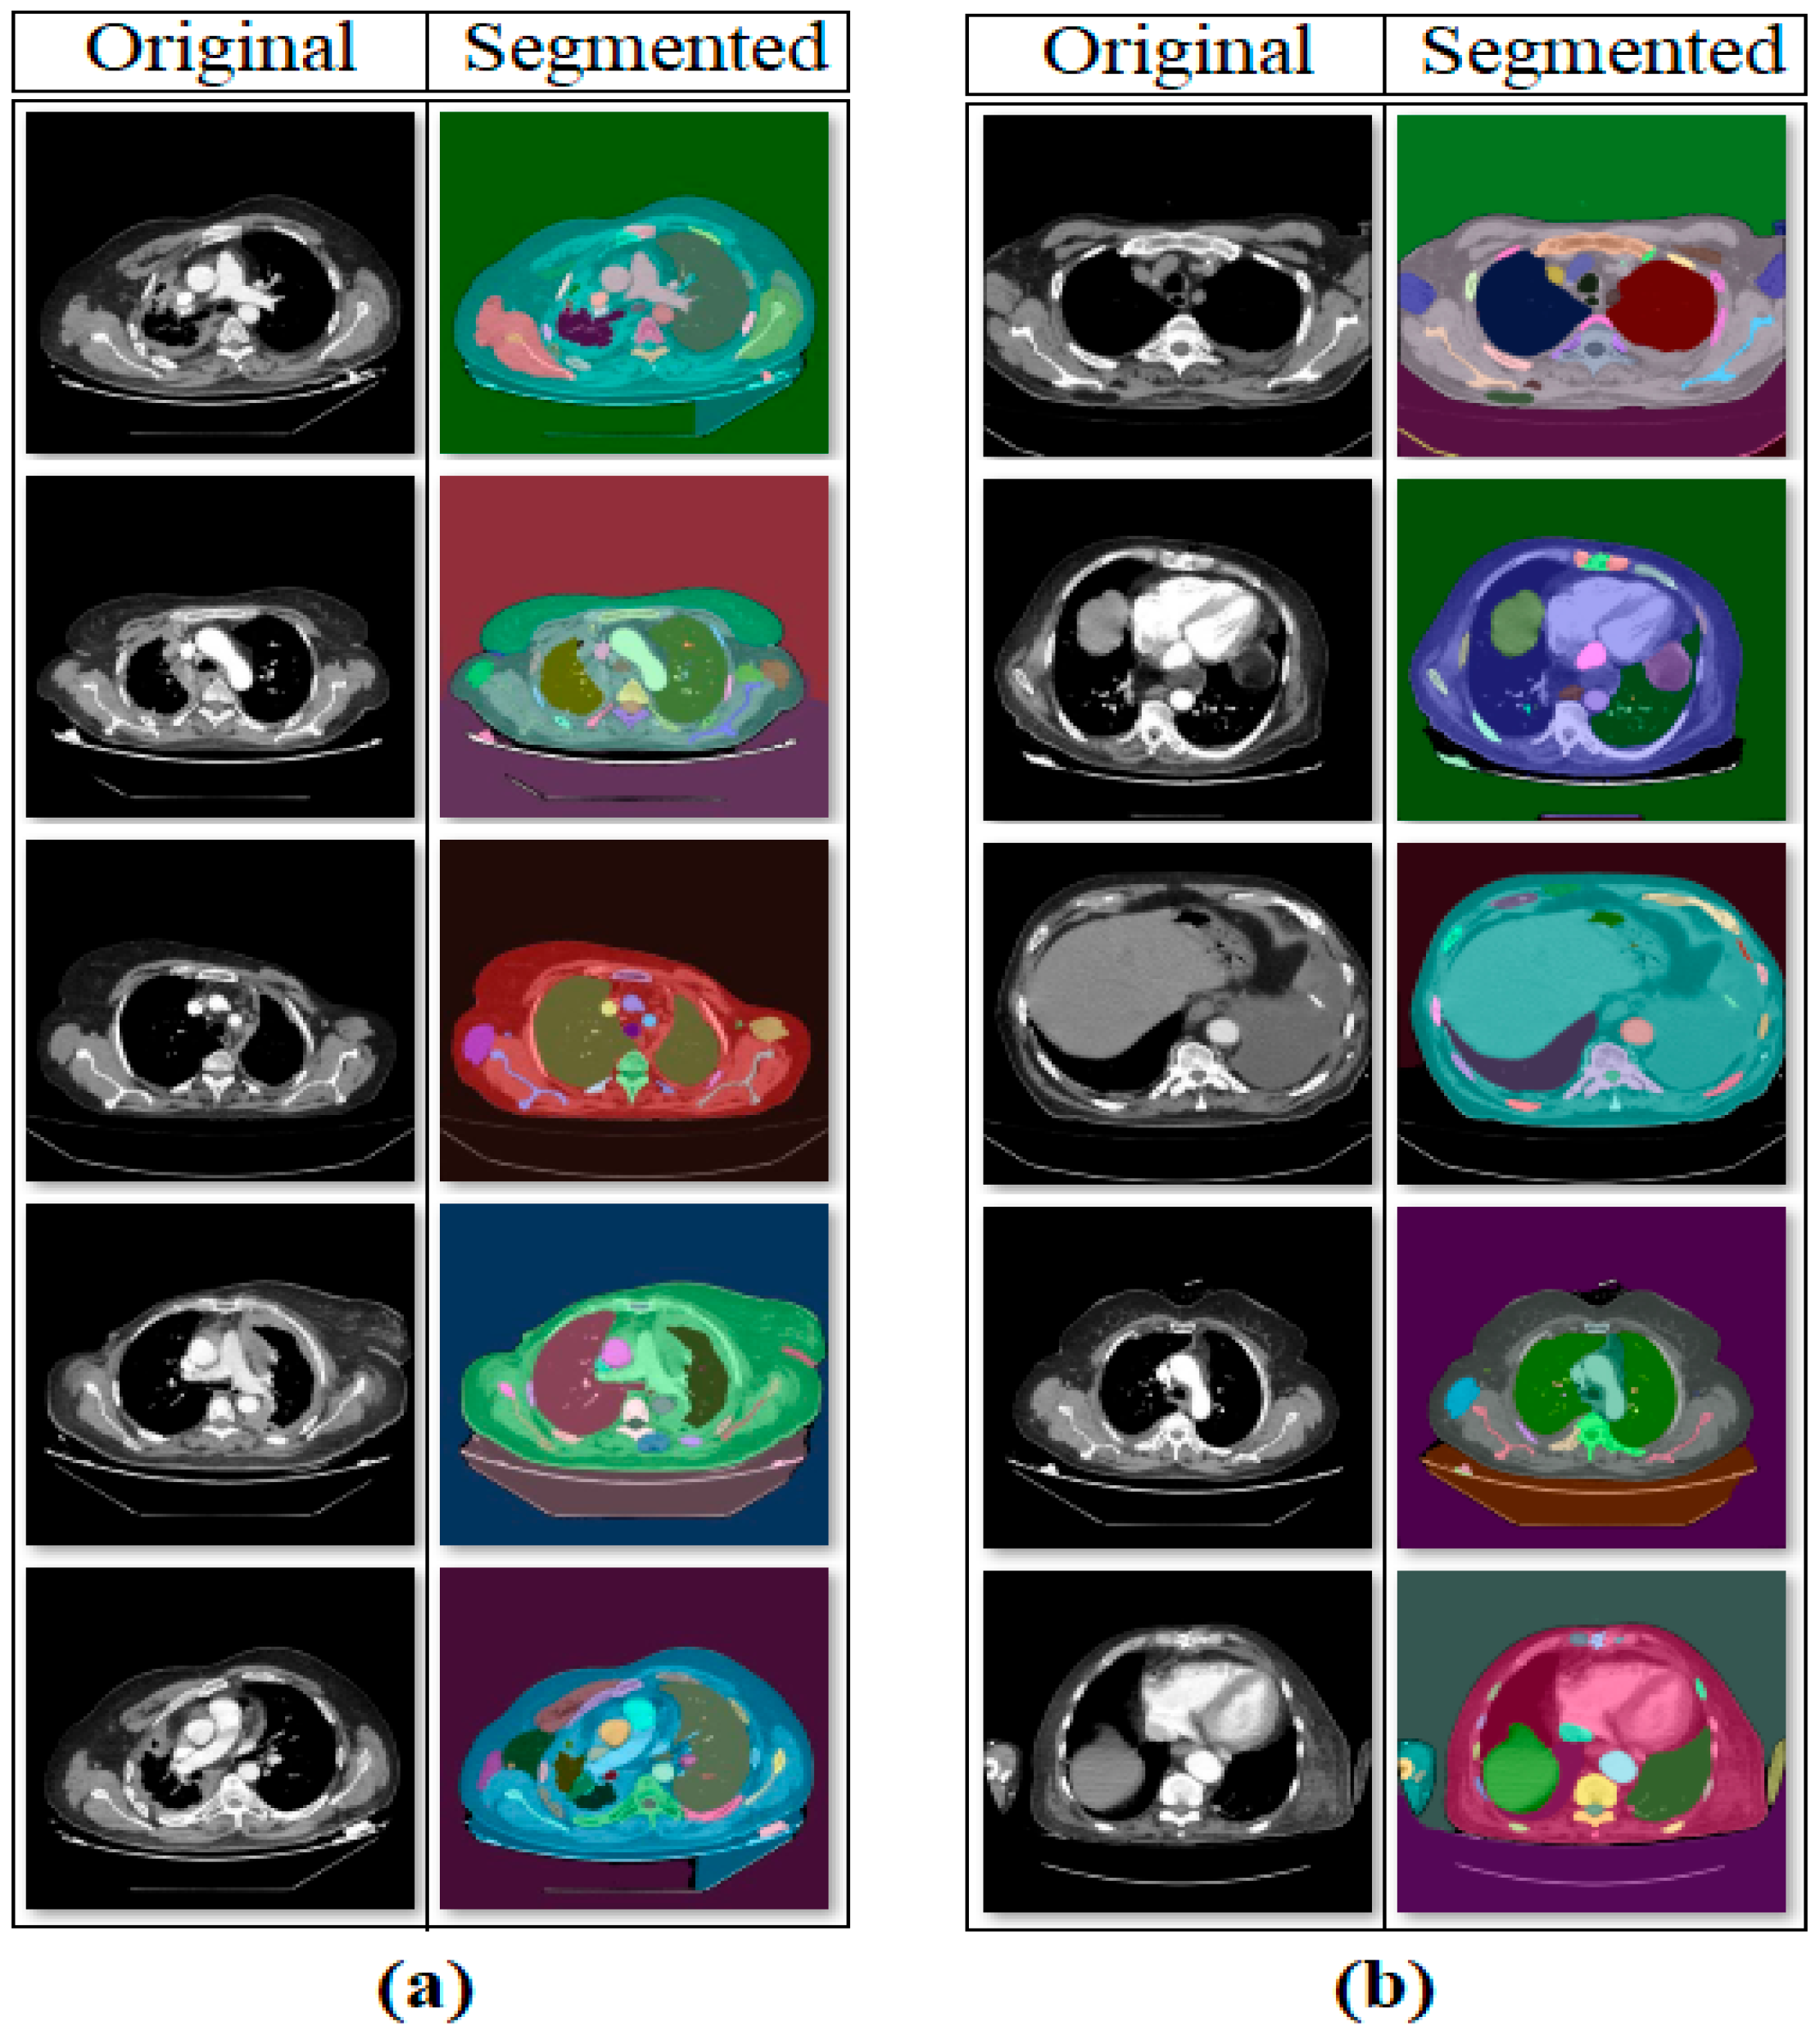

2.2. Segment Anything Model

- Meaningful regions were highlighted in CT images using the SAM method; deep learning models were enabled to focus on these regions and leave meaningless regions in the background.